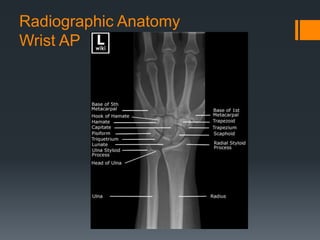

Radiographic Anatomy

Wrist AP